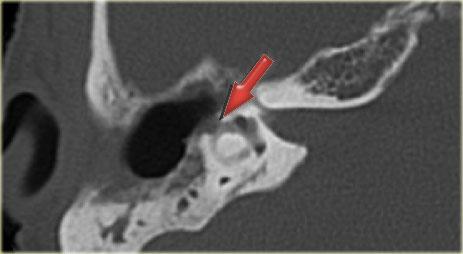

Bên trái là các ảnh cắt coronal của cùng một bệnh nhân.

Bên phải, động mạch cảnh trong tách biệt hoàn toàn với tai giữa (mũi tên xanh dương).

Bên trái, động mạch cảnh trong đi xuyên qua tai giữa (mũi tên đỏ).